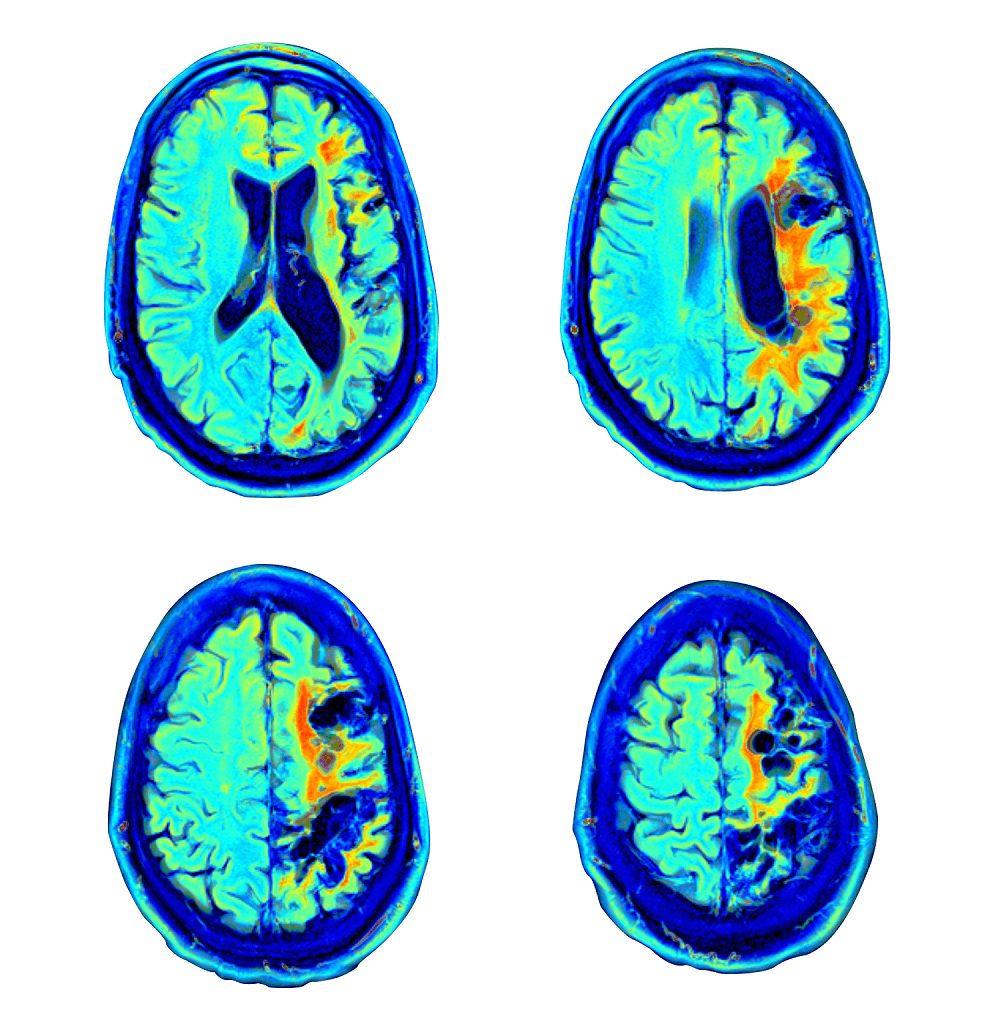

تقييم طبي وفسيولوجي دماغي شامل، يجريه مركز التميّز الذهني والبدني بالاعتماد على الطاقم الطبي المكون من الأطباء، وأخصائيي الدماغ والأعصاب، وأخصائيي العلاج الطبيعي، والممرضات. ويتألف التقييم من اختبارات تصوير الدماغ المتقدمة التي تتناسب مع احتياجات المريض، وتشمل التصوير بالرنين المغناطيسي عالي الدقة للدماغ، والاختبار الذهني المحوسب، والتقييم الشامل للأعراض السريرية. كما يتضمن اختبارات متقدمة لتحليل طريقة المشي وأساليب التصوير المناسبة لاحتياجات طفلك - بما في ذلك التصوير بالرنين المغناطيسي للدماغ MRI والتصوير المقطعي بالإصدار البوزيتروني SPECT.